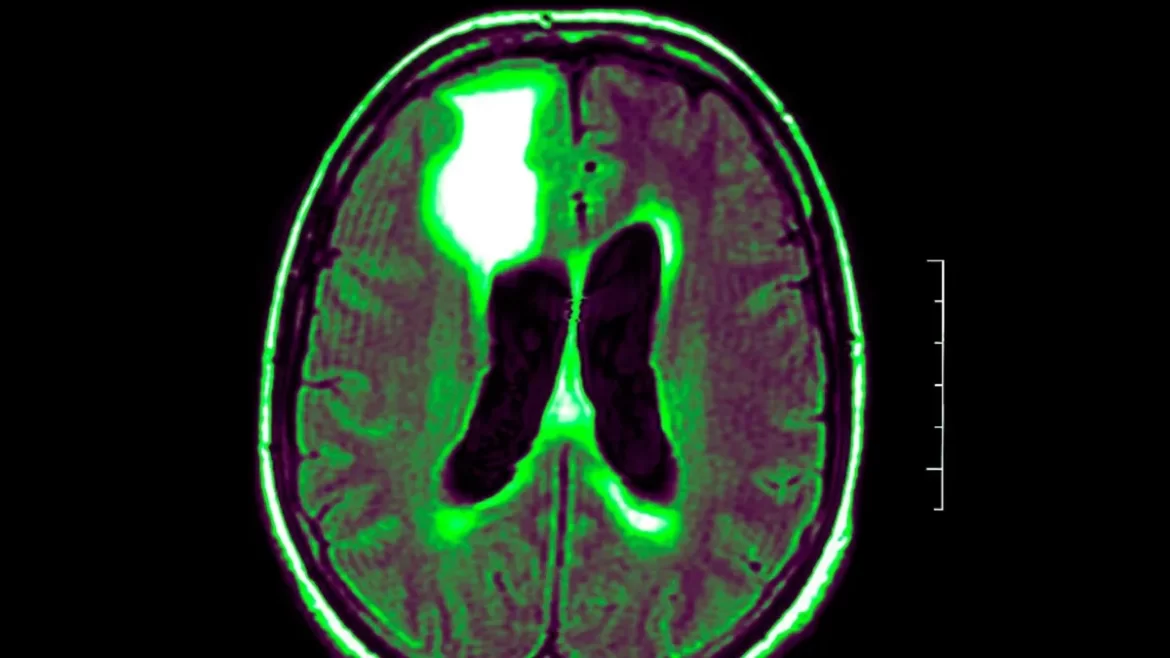

In transcranial photobiomodulation (tPBM), non-ionizing radiation sources such as light-emitting diodes (LEDs) or visible and infrared light are used to directly target specific regions of the brain. There is some evidence to suggest that this therapy may alleviate symptoms associated with illnesses of the central nervous system. Although researchers have had trouble assessing tPBM’s efficacy, they have identified dose as a potential problem. Evidence has emerged, as standardization has improved, that tPBM does influence metabolic activity in certain brain regions.

Studies in animals and people have shown that TPBM increases brain oxygen consumption, blood flow, and metabolic energy generation. Evidence from mice models suggests that tPBM may enhance cognition in people with dementia or Alzheimer’s disease. TPBM may also boost neuroprotection via numerous methods.

Memory is enhanced and brain oxygenation and activity are boosted by tPBM in rats. Cognitive and memory enhancement, and even reversal of memory problems, have been shown in several animal models when tPBM was administered.